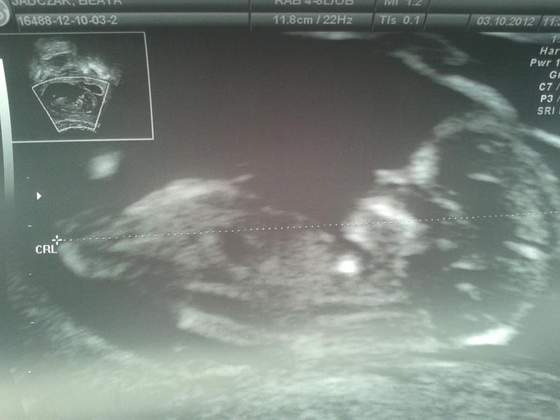

a chciałam pokazać moją kruszynkę. Z miesiączki wychodzi na 18 kwietnia a z usg na 16

nie jestem, właśnie miała do Ciebie pisać. Kurcze nie umiem dodać zdjęciaa chciałam pokazać moją kruszynkę. Z miesiączki wychodzi na 18 kwietnia a z usg na 16